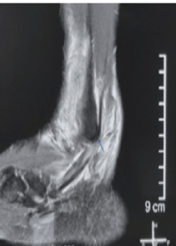

Split Peroneus Brevis: An Overlooked Cause of Ankle Dysfunction

Kumardev Arvind Rajamanya , Rahul Shah , Tushar Nayak

………………………………p.27-31